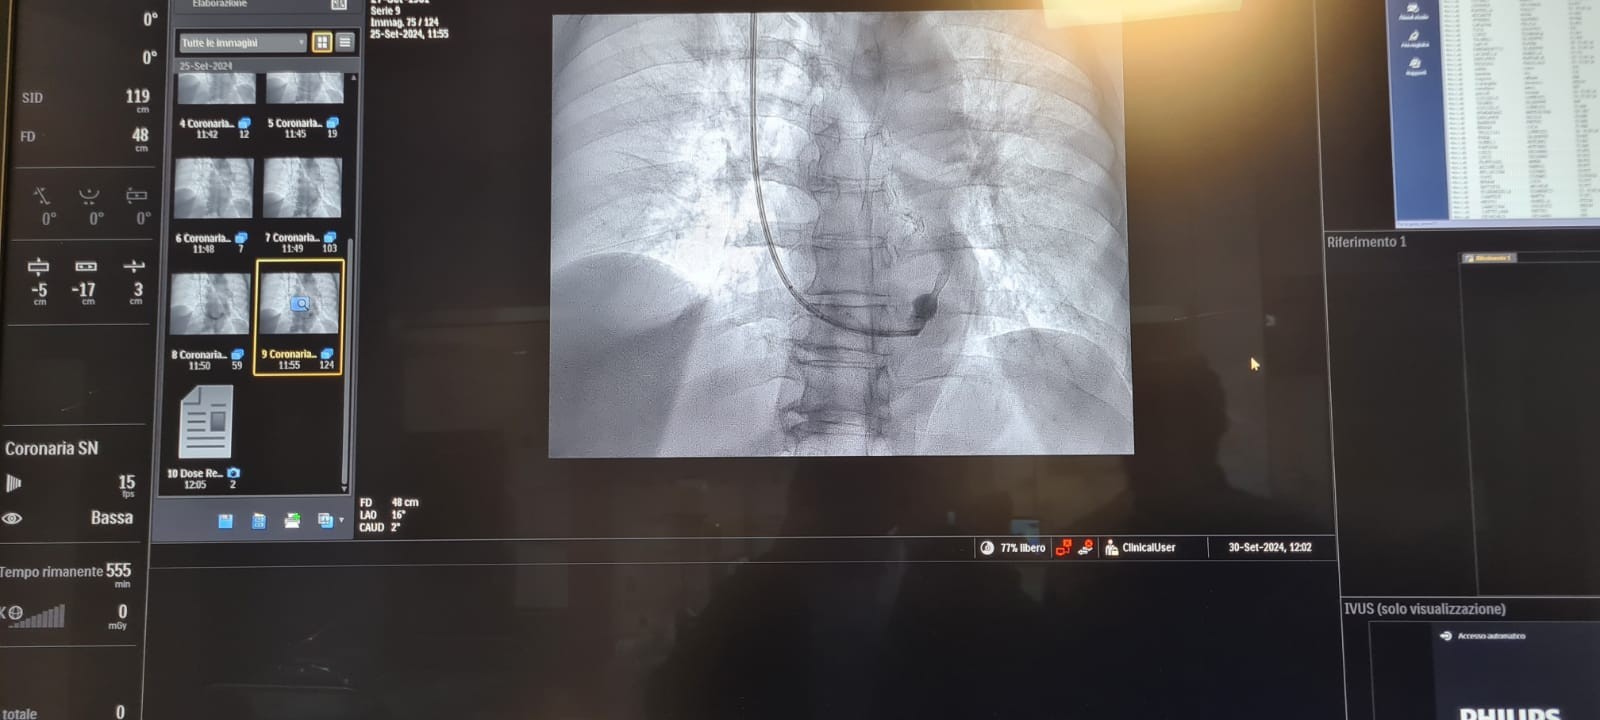

Un intervento chirurgico programmato con il supporto dell’intelligenza artificiale è stato eseguito con successo all’ospedale Ospedale Di Venere di Bari. Lo ha reso noto la Asl Bari, spiegando che si tratta del primo intervento di riparazione endovascolare di aneurisma dell’aorta addominale pianificato attraverso sistemi di analisi predittiva e tecnologia “Digital Twin”, il cosiddetto “gemello digitale”. […]